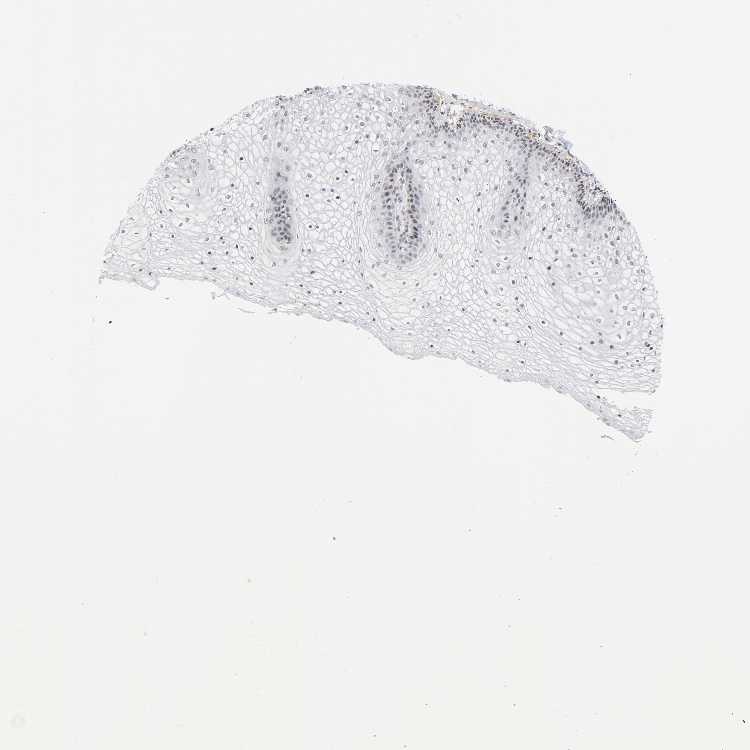

TISSUE PRIMARY DATA VAGINA Show tissue menu

VAGINA - Antibody stainingi

Antibody staining in the annotated cell types in the current human tissue is reported as not detected, low, medium, or high, based on conventional immunohistochemistry profiling in selected tissues. This score is based on the combination of the staining intensity and fraction of stained cells.

Each image is clickable and will lead to virtual microscopy that enables deeper exploration of all samples and also displays staining intensity scores, fraction scores and subcellular localization as well as patient and tissue information for each sample.

Antibody HPA049904Antibody CAB004374

Squamous epithelial cells HighMedium